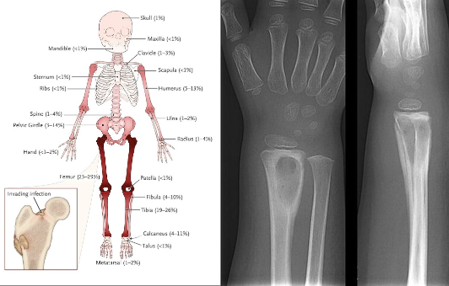

Osteomyelitis

Defined as an infectious process in the bone that can occur at any age, but is most commonly seen in children 10 years and younger.

Causes:

Direct inoculation (break in the skin → pathogen enters)

Abscess

Dead bone

Clinical Symptoms:

Malaise, low-grade fever

Irritability (especially in infants and non-verbal children)

Edema

Erythema

Joint tenderness

Decreased use

Limp

Refusal to walk (woke up not wanting to walk)

Fever

Children may c/o their knee hurting when its actually their hip and vice versa.

Diagnosis:

Bloodwork:

For acute: Elevated ESR and CRP

WBC count may be non-specific (acute = elevated; chronic = may be normal)

Imaging:

Deep tissue swelling, periosteal elevation, lytic sclerosis.

Bone biopsy may be necessary.

Nursing Management:

Administer IV antibiotics. (for a long time)

Provide pain medications as needed.

Enforce activity restrictions and immobilization.

Provide post-op care after surgical debridement. (5 Ps)